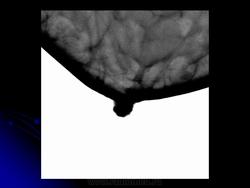

Со старением железистая ткань постепенно исчезает: прозрачность жировой ткани становится преобладающей с несколькими каркасами, связанными с опорными волокнистыми структурами.

Жирная (не плотная) грудь

Умеренно плотная грудь

Плотная грудь

Маммограммы представляют собой изображения структур, проецируемых на плоскость: плотная грудная маммограмма, следовательно, состоит из многих других структур, которые необходимо проанализировать, чем более жирная, пустая грудь. По этой причине диагностировать рак молочной железы труднее для моложе, чем для пожилых женщин.

Нажмите на миниатюрные картинки, чтобы получить увеличенный размер.